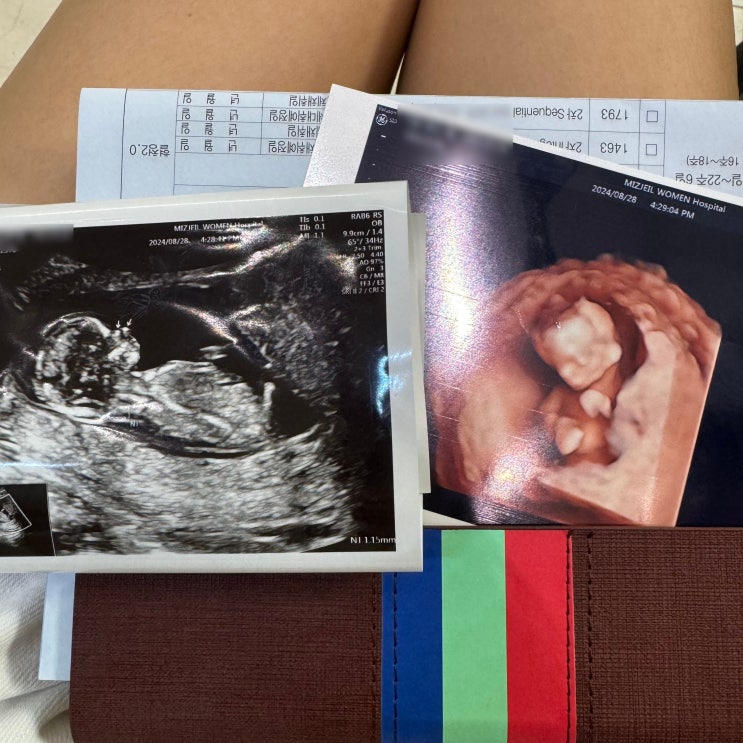

[임신 일기] 좌충우돌 임신 중기 - 15주부터 18주의 기록 (+젠더 리빌, 임산부 다래끼, 첫 태동, 임산부 화상, 아기 침대, 미즈제일 기형아 검사)

평온하게 흘러간다는 임신 중기 나는 유별나게도 별일이 참 많았다. 사실 평소라면 큰일이 아니었는데, 임...

[임신 일기] 무탈하게 지나간 임신 초기 8주부터 14주까지의 기록 (+대전 마리아 졸업, 분만병원 전원, 1차 기형아 검사, 12주 성별 확인, 장꾸맘 각도법, 근종통)

아기집을 확인하고 심장 소리를 여러 번 들어도 아직 내 배속에 들어있는 게 한 생명체라고 믿기지 않는 임...